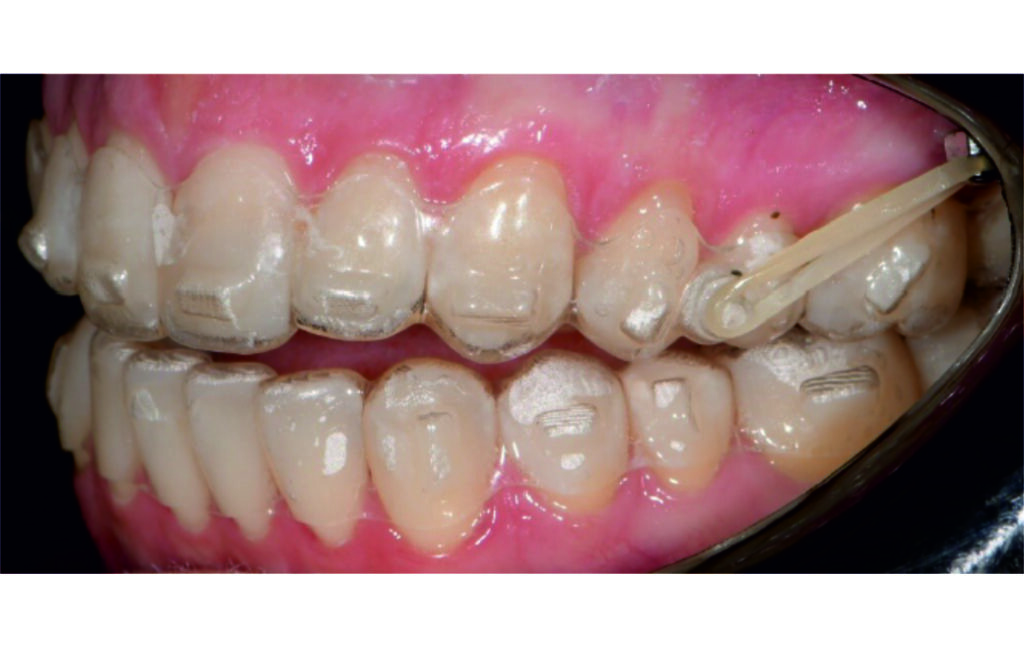

A 1.5 mm deviation of the upper dental midline to the patient’s left was noted, along with a slight mandibular midline shift to the right, likely due to asymmetrical mandibular growth observed in the facial structure. Severe mesial rotations of teeth 16 and 26 were evident in the initial records. As derotation of 16, 26, 17, and 27 progressed up to aligner 16, the premolars in segments I and II moved distally, resulting in a bilateral Class I relationship, as intended in the initial treatment plan.

Derotation of 16 26 allowed Class II correction.

Vertical vector of elastic traction on buttons and IZC helped with the open bite correction.

An infrazygomatic crest (IZC) screw with force applied between the upper premolars produces a clockwise rotation of the maxillary occlusal plane. This movement aids in closing the anterior open bite and improves upper incisor display. IZC screws with elastics also enable planned intrusion of the upper molars by 1 mm. Because mandibular derotation after upper posterior correction is difficult to predict, anterior distalization and midline correction were performed in the later stages of treatment.